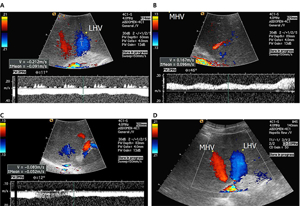

- 도플러 초음파 검사 (Doppler Ultrasound)

- 일반 초음파의 원리에 도플러 효과를 적용한 검사로, 움직이는 혈액의 속도와 방향을 실시간으로 측정할 수 있습니다.

- 혈관 내 혈류의 특성을 분석해 혈류가 정상적으로 흐르는지, 역류나 협착이 있는지 평가할 수 있습니다.

- 혈관의 기능적 상태를 파악하는 데 중요한 역할을 하며, 하지정맥류, 동맥 협착, 혈전 등 혈관 질환 진단에 쓰입니다.